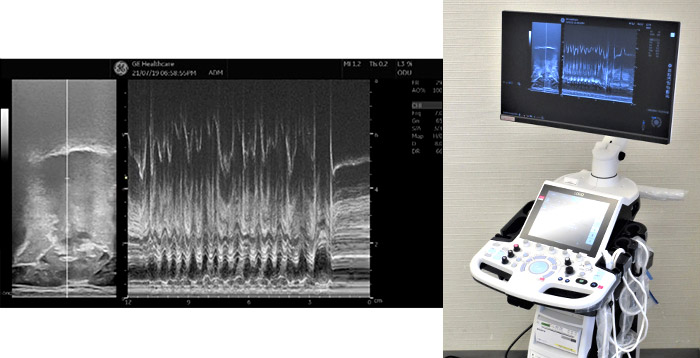

1)超音波検査を用いた舌の研究

食べているときに舌はどのように動いているのでしょうか?身近なのに未解明なことが多い舌についての研究です。内科や産婦人科で用いられている超音波画像検査(エコー)を利用して、食べている最中の舌運動を観察、比較することで舌の動きの解明や口腔リハビリテーションへの応用に繋がると考えています。

超音波診断装置